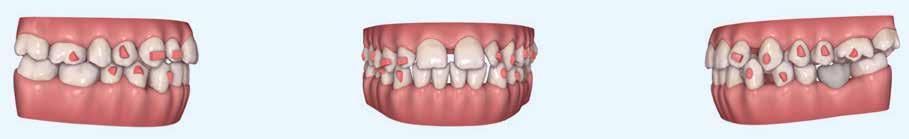

A kezelést Pitts-21-es fogszabályozó készülék alkalmazásával végeztük el. A felső fogíven mosolyvonal beállító esztétikai (Smile Arc Protection - SAP), az alsó fogíven a Spee görbe kiegyenlítését szolgáló funkcionális bracket pozicionálást

alkalmaztunk. Előbbi elengedhetetlen a szép, íves mosolyvonal kialakításához, utóbbi pedig az alsó fogsor mezializálásához, és így az első osztályú sagittális okklúzió kialakításához. Az alsó metszők torlódásának feloldására tolórugókat alkalmaztunk az első hónapban (8. kép)

A protokollok szerves része a mesterséges harapásemelés, melynek segítségével – mintegy kivéve a rágóerők fogmozgatásokat akadályozó hatását – segítjük fogszabályozó rendszer működését. Ezek a ragasztásnál az alsó 7-esekre, majd később a felső 4-esekre kerültek (9. kép).

A harapást beállító elasztikus gumihúzásokat, mint minden kezelésnél, ebben az esetben is folyamatosan, az egész ke-

zelés alatt 24 órában (étkezések kivételével) viselte a páciens. Segítségükkel történt az alsó fogsor mezializálása, és a harapásemelésben is fontos a szerepük a disztálharapás korrekciója során. Az utolsó hónapokban az okklúziós finomítások is részben a segítségükkel történnek az ívhajlítások mellett (10. kép).

A fogkontúrálás és az interproximális redukció alkalmazásával a mikroesztétikai részletek tökéletesítése is megtörtént (11. kép) A kezelés mindössze 16 hónapig tartott, megtörtént a rágófunkció helyreállítása, és az esztétikai végeredmény sokéves várakozás után valóban fordulópontot jelentett páciensünk életében (12-14. képek).

A fogszabályozás aktív fázisa után minden kezelésnél a retenció, a passzív helyben tartó fázis legalább annyira fontos, mint az előtte történtek, továbbá a fogak pozíciójának, de a beállított harapás stabilitásának a segítése is.

Előbbi elérésében az ún. essix retainerek, az egy fogívre kiterjedő mélyhúzott sínek tartják a felső és alsó fogívben a fogakat a beállított pozíciójukban, a felső és alsó frontfogakra orálisan ragasztott fix retainerek mellett (15. kép).

A harapás sagittális rögzítésében elengedhetetlen szerepe van az ún. Pitts Izom Tréning Splintnek, amelyben a páciens összeharap, így az megakadályozza az alsó fogsor visszamozdulását a disztálharapásos helyzetbe (16. kép).